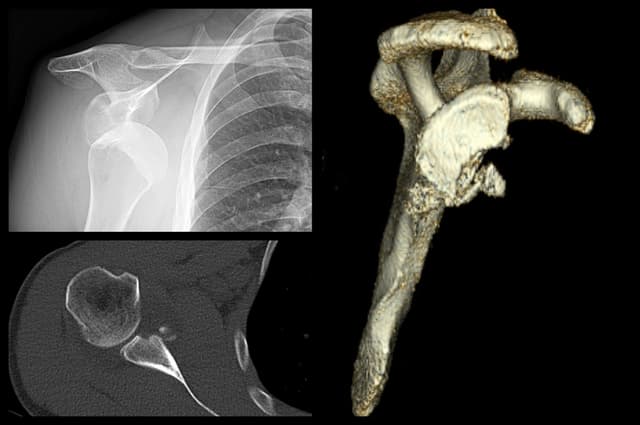

Glenoid Reconstruction with Allograft

Imaging

Pre-op